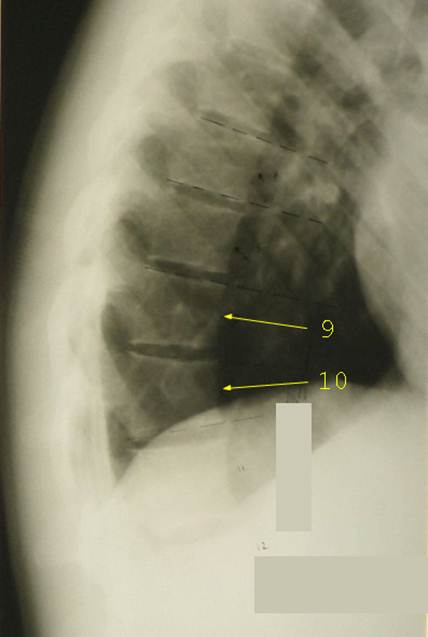

Боковая

рентгенограмма позвоночника здорового ребенка 8 лет. Обратите внимание, что начали

прослеживаться тени ядер окостенения апофизарных колец (некоторые из них

отмечены зелеными стрелками). Форма тел верхних грудных позвонков очевидно клиновидная, причем угол

клиновидности составляет 5 – 7 градусов. Тела нижних грудных позвонков имеют

несколько овоидную форму с отчетливым сужением кпереди. Подобная картина является нормальным явлением

для детей в возрасте 8 – 12 лет. При выставлении диагноза компрессионного

перелома тела позвонка следует опираться

не только на рентгенологическую картину, но и на данные анамнеза и клинического

осмотра.

Компрессионный

перелом 9 и 10 грудных позвонков у девочки 16 лет, получившей кататравму –

падение со второго этажа. Клиновидность тела десятого грудного позвонка

составляет 15 градусов, девятого – 9 градусов. Пострадавшая жаловалась на

сильнейшие боли в спине при постукивании в области остистых отростков этих

позвонков, а также при любых движениях.

Диагноз компрессионного перелома тел 9 и 10 грудных позвонков не

вызывает сомнений. Удивительно, но никаких других повреждений, кроме обширного осаднения кожи спины и левого

бедра, больше не обнаружилось.